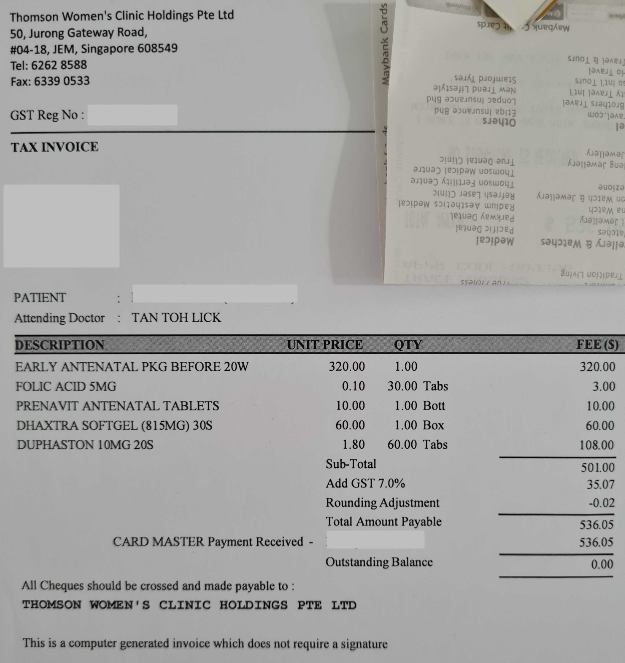

シンガポールで妊婦検診②

はじめての妊婦検診から4日後(11/16)

小さな小さな胎嚢がしっかりと子宮内で確認できました😊💕

まだ心拍は確認できないですが

👶のためにサプリ、食べ物からどんどん栄養を送っていこうと思います😚笑

~本日のお会計~

大したことを相談してないのに、毎回Consult Feeとして$80取られるのはちょっと....

~サプリメント~

Prenavit antenatal tablets

必要なビタミンとミネラルを摂取するために処方されたサプリメント

1日1錠

Duphaston10 MG

切迫流産、習慣性流産の予防のためのサプリメント

1日3錠(朝、昼、夜)